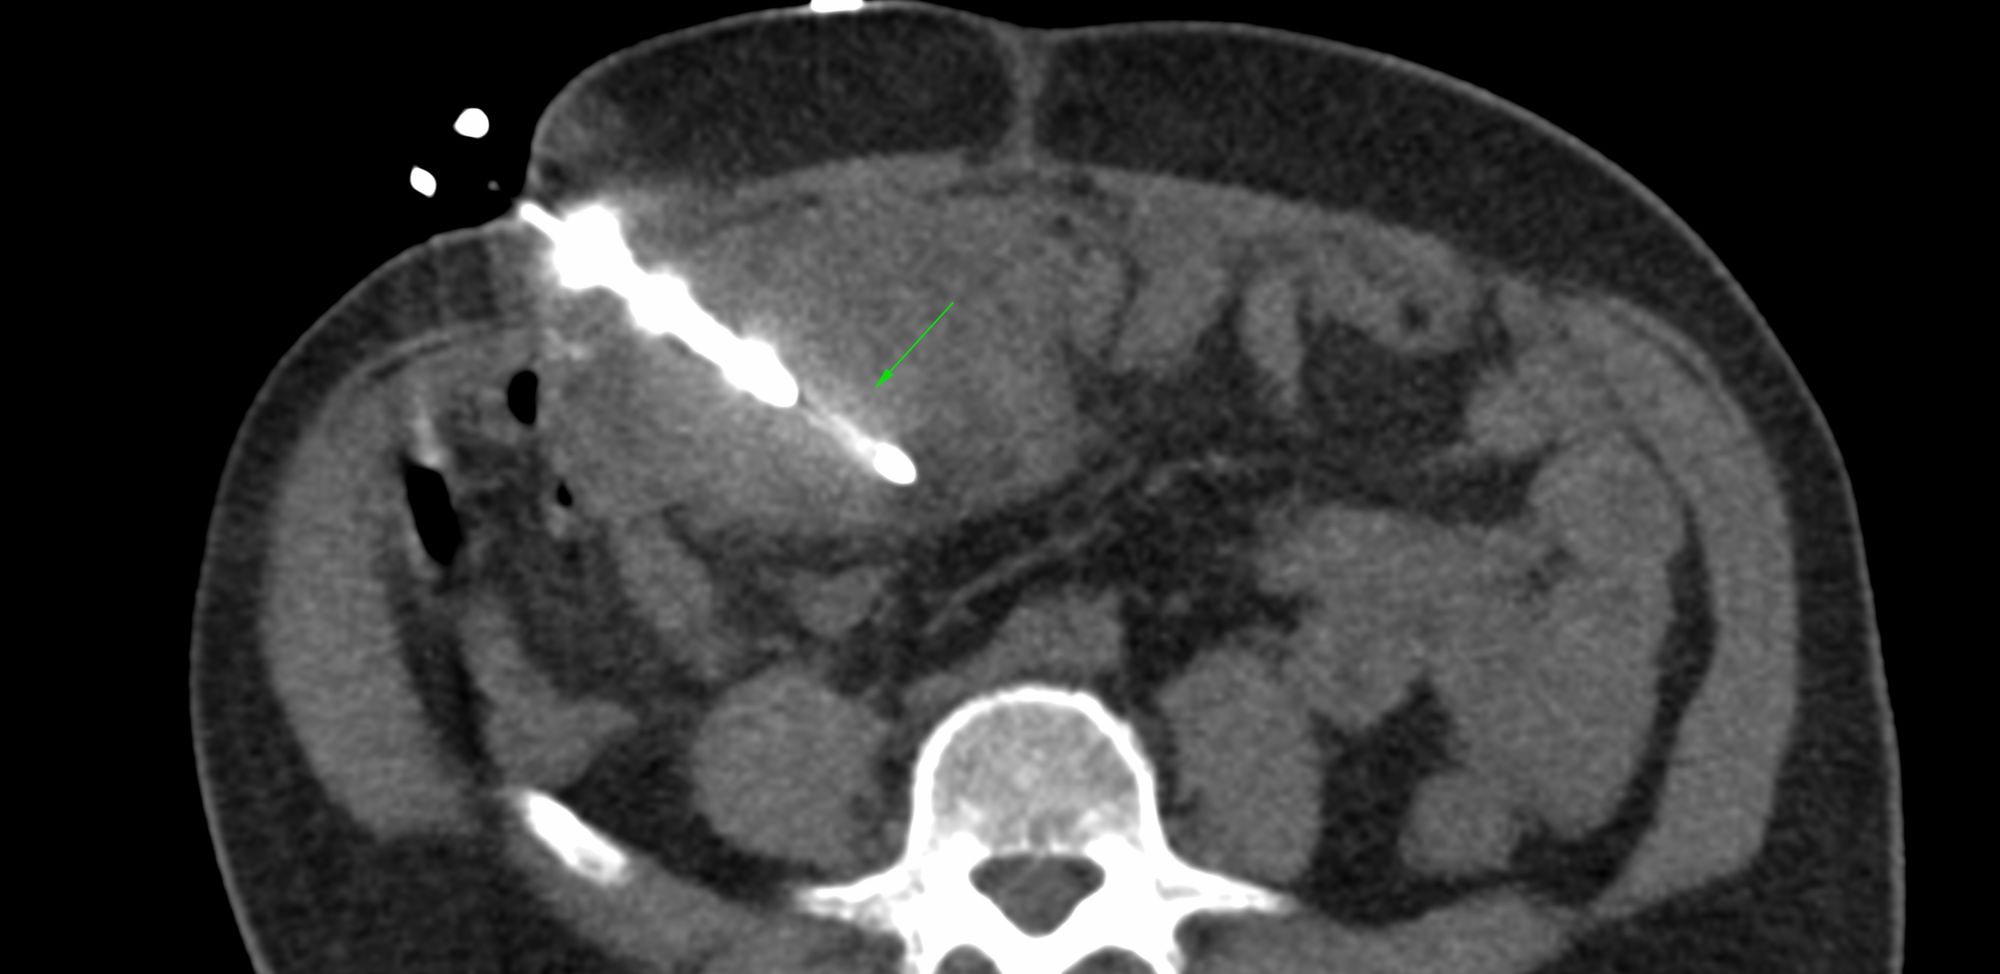

Case 95: Omental Nodule Biopsy